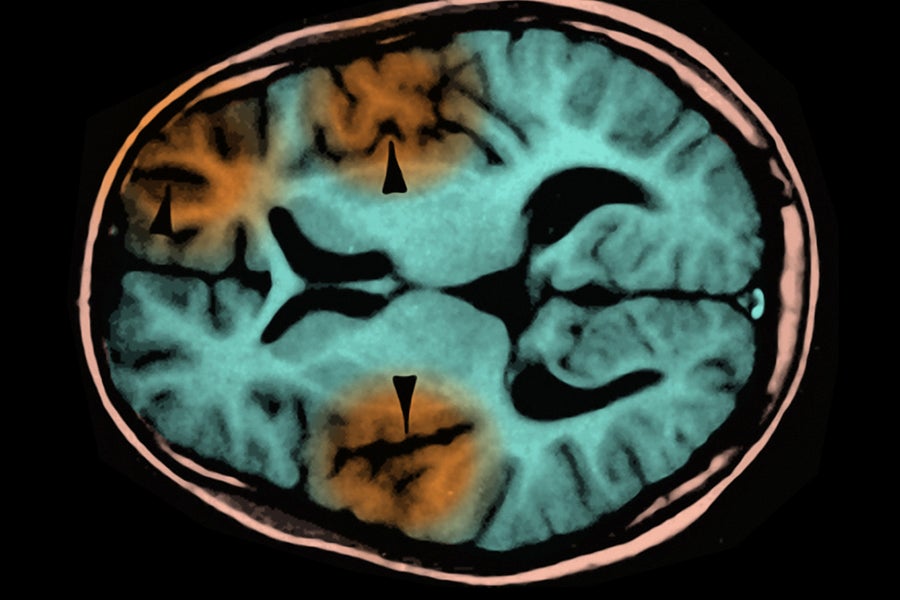

The child who died suffered from subacute sclerosing panencephalitis (SSPE), a progressive brain disorder that usually develops two to 10 years after a measles infection. The measles virus appears to mutate into a form that avoids detection by the immune system, allowing it to hide in the brain and eventually destroy neurons.

People with SSPE experience a gradual, worsening loss of neurological function and usually die within one to three years after diagnosis, according to the Los Angeles County Health Department. The disorder affects only about one in every 10,000 people who contract measles. But the risk may be as high as about one in 600 for those who are infected as infants.

SSPE is one of several side effects of measles that go beyond the coughing, runny nose, and characteristic rash of the original infection. Measles can also cause encephalitis, a faster-occurring brain inflammation, in one in every 1,000 people who are infected because the virus causes the immune system to attack a protein produced by certain brain cells. This inflammation kills about one in five people who develop it.

An MRI scan showing subacute sclerosing panencephalitis, a complication of measles infection. Science Source